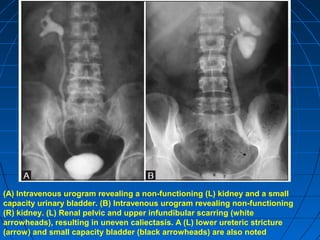

(A) Intravenous urogram revealing a non-functioning (L) kidney and a small

capacity urinary bladder. (B) Intravenous urogram revealing non-functioning

(R) kidney. (L) Renal pelvic and upper infundibular scarring (white

arrowheads), resulting in uneven caliectasis. A (L) lower ureteric stricture

(arrow) and small capacity bladder (black arrowheads) are also noted

(A) Intravenous urogramrevealing a non-functioning (L) kidney and a small capacity urinary bladder. (B) Intravenous urogram revealing non-functioning (R) kidney. (L) Renal pelvic and upper infundibular scarring (white arrowheads), resulting in uneven caliectasis. A (L) lower ureteric stricture (arrow) and small capacity bladder (black arrowheads) are also noted